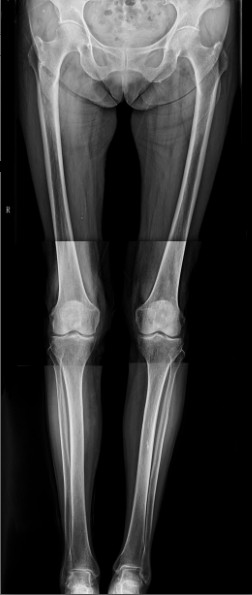

病例二:患者女性,82歲。主因“右膝疼痛10年伴加重、活動(dòng)受限半個(gè)月”入院。入院前右膝痛時(shí)好時(shí)壞,疼痛劇烈時(shí)無法站立。

患者術(shù)前全長

患者術(shù)后

患者術(shù)后全長